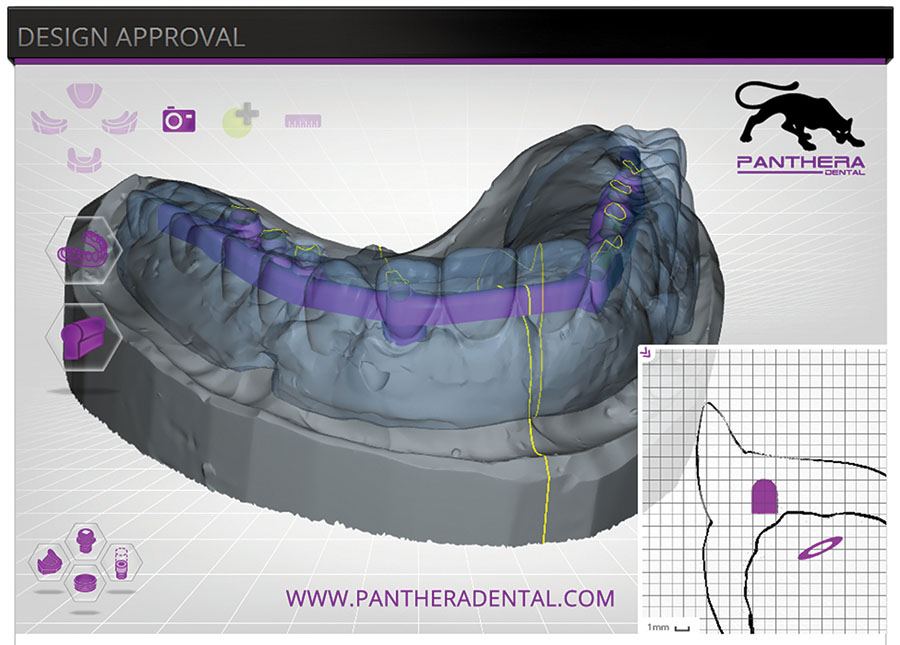

Implant Treatment with Integrated Solutions for Efficient Workflows

Dentsply Sirona’s integrated solutions for implant dentistry enable dental professionals to deliver safer and more efficient treatment processes as well as increased comfort and improved quality of life for their patients. The merger between DENTSPLY and Sirona has brought together two companies with long-term expertise in their respective fields, providing innovative and clinically tested technology, … Read more